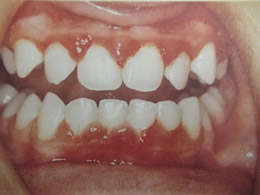

Ουλίτιδα

Η νόσος της ουλίτιδας:

- Εκδηλώνεται με διόγκωση και ερυθρότητα των ούλων γύρω από τα δόντια.

- Το κυριότερο χαρακτηριστικό είναι η αιμορραγία των ούλων στο βούρτσισμα και ορισμένες φορές συνοδεύεται από πόνο και κακοσμία του στόματος.

- Οφείλεται, όπως και η τερηδόνα, στη μικροβιακή πλάκα δηλαδή στα μικρόβια που προσκολλώνται στα δόντια και τα οποία έρχονται σε επαφή με τα ούλα προκαλώντας τοπικά φλεγμονή.

- Μπορεί εύκολα να προληφθεί με σωστό και καθημερινό βούρτσισμα των δοντιών, τη χρήση οδοντικού νήματος και των στοματικών διαλυμάτων σύμφωνα με της οδηγίες του παιδοδοντίατρου. Σημαντικός είναι επίσης ο τακτικός έλεγχος των δοντιών στον παιδοδοντίατρο και ο καθαρισμός των δοντιών 1-2 φορές το χρόνο.